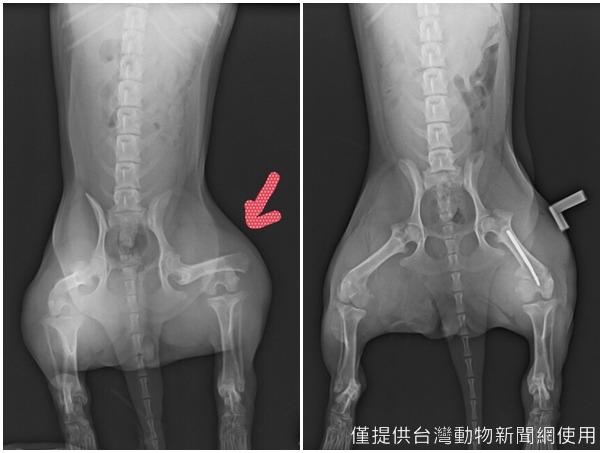

而另一位張小姐則是希望呼籲飼主要定期檢查牽繩並更換,因為去年底張小姐的爸爸一早帶家中的臘腸Mato散步,雖然有使用牽繩,卻因為牽繩靠近扣項圈處的接縫突然斷裂,意外讓當時在奔跑中的狗狗竄到馬路上遭機車撞傷。

好加在狗狗僅後腿大腿骨折,緊急送到動物醫院後,醫生表示打骨釘即可,目前Mato也正在養傷當中,不過張小姐仍相當心疼狗狗遭逢意外,更希望用自己的親身案例提醒更多飼主使用牽繩、檢查牽繩的重要性。